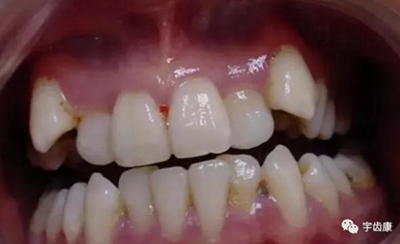

6. 保護(hù)牙周組織

牙體解剖知識

牙體各個面的解剖厚度